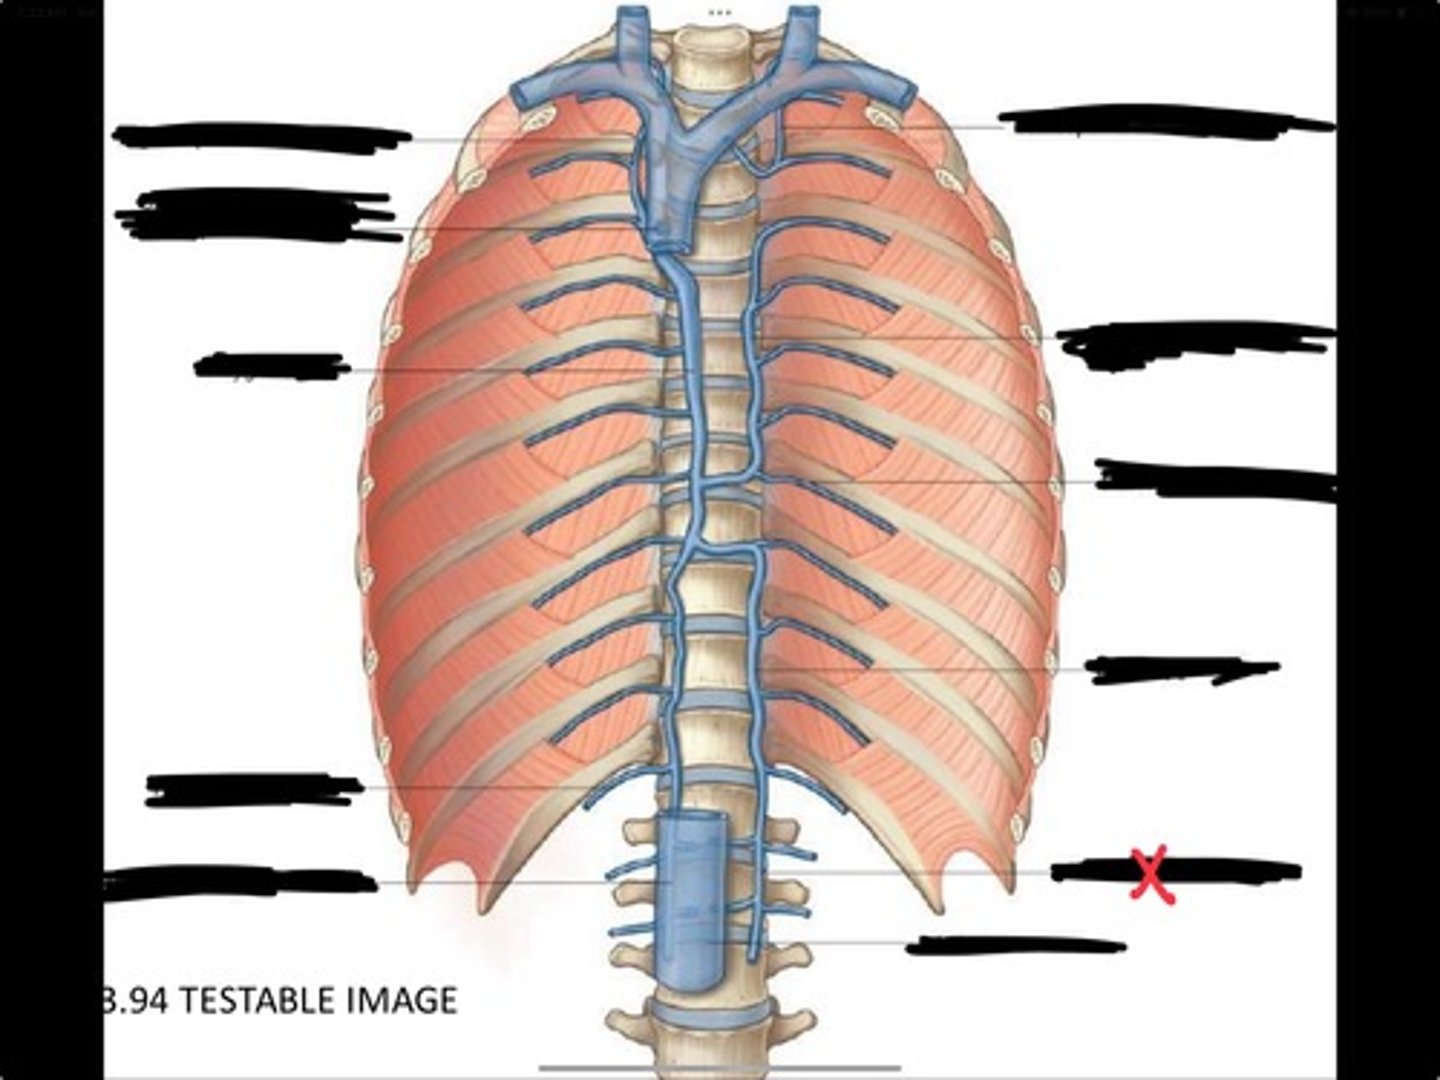

Right ascending lumbar vein

Right subcostal vein

Azygos vein

Opening of the azygos vein into superior vena cava

Right superior intercostal vein

Left superior intercostal vein

Accessory hemiazygos vein

Posterior intercostal vein

Hemiazygous vein

Ascending lumbar vein